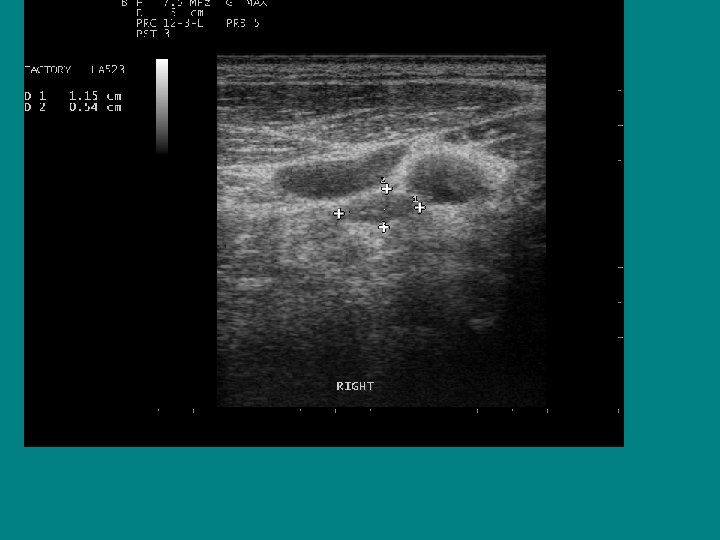

SEARCH FOR RECURRENT/RESIDUAL DISEASE • HYPOECHOIC MASS, LIKELY LYMPH NODE • AP/T 0. 7 CM !!

Ultrasound characteristics of a benign lymph node Ø Flattened or oval ( AP/T < 0. 5 Ø Echogenic Hilus Ø Hilar Flow on Doppler

Best ultrasound criteria for malignancy • Short to long axis diameter ratio of more than 0. 5 • It has 75 % sensitivity, 81 % specificity • 79 % accuracy

Does size help predict a malignant lymph node? • NO ! • Size doesn’t matter, • Border doesn’t help either

AP/T 0. 79/1. 45= 0. 54 !